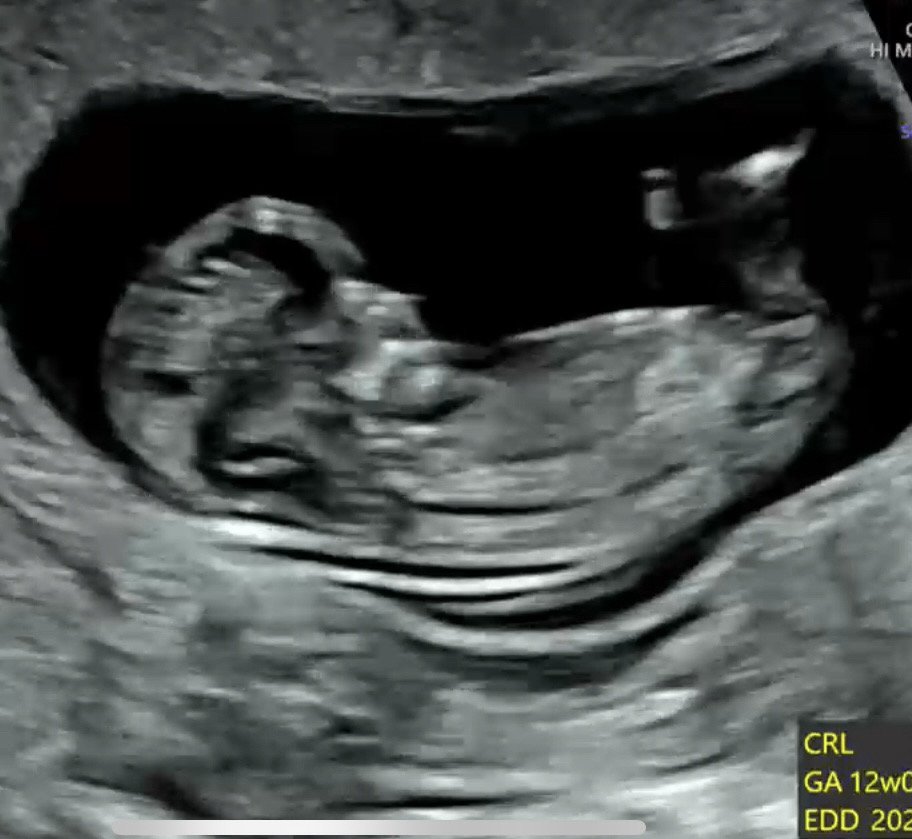

11주5일 각도법, 빌리는 딸이라는데 헷갈려요 투표 부탁드려요!

딸일까요 아들일까요?? 각도법 고수님들 부탁드려용